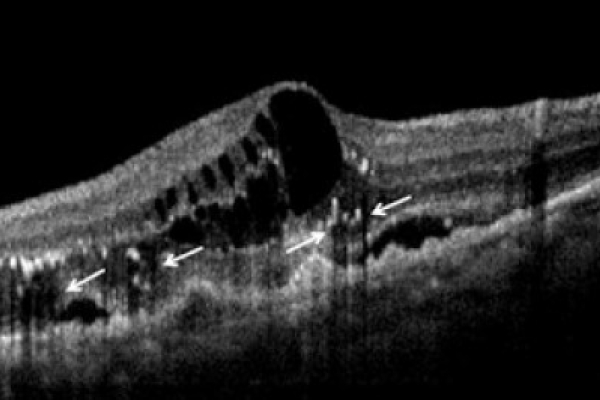

Analisi dell’OCT strutturale nella patologia maculare. Aspetto complessivo

delle immagini OCT

· Morfologia. Analisi qualitativa dell’OCT strutturale patologico

· Reflettività analisi qualitativa dell’OCT strutturale patologico

· Zone d’ombra – e$etto schermo